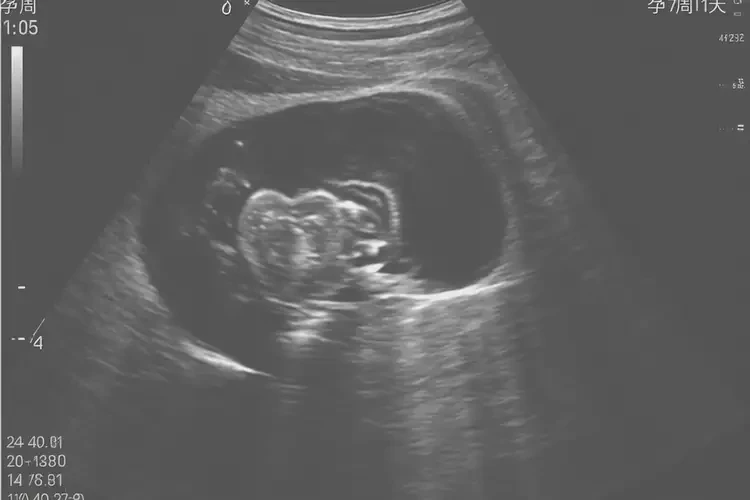

孕7周1天胎心率168怎么回事

胎心率168次/分鐘

孕7周1天的胎心率達(dá)到168次/分鐘,屬于正常范圍。胎心率是指胎兒心臟每分鐘跳動的次數(shù),通常在孕早期(6-10周),胎心率會較快,范圍在150-190次/分鐘之間。

孕7周1天胎心率168怎么回事(圖1) 孕7周1天胎心率168怎么回事(圖2) 孕7周1天胎心率168怎么回事(圖3)